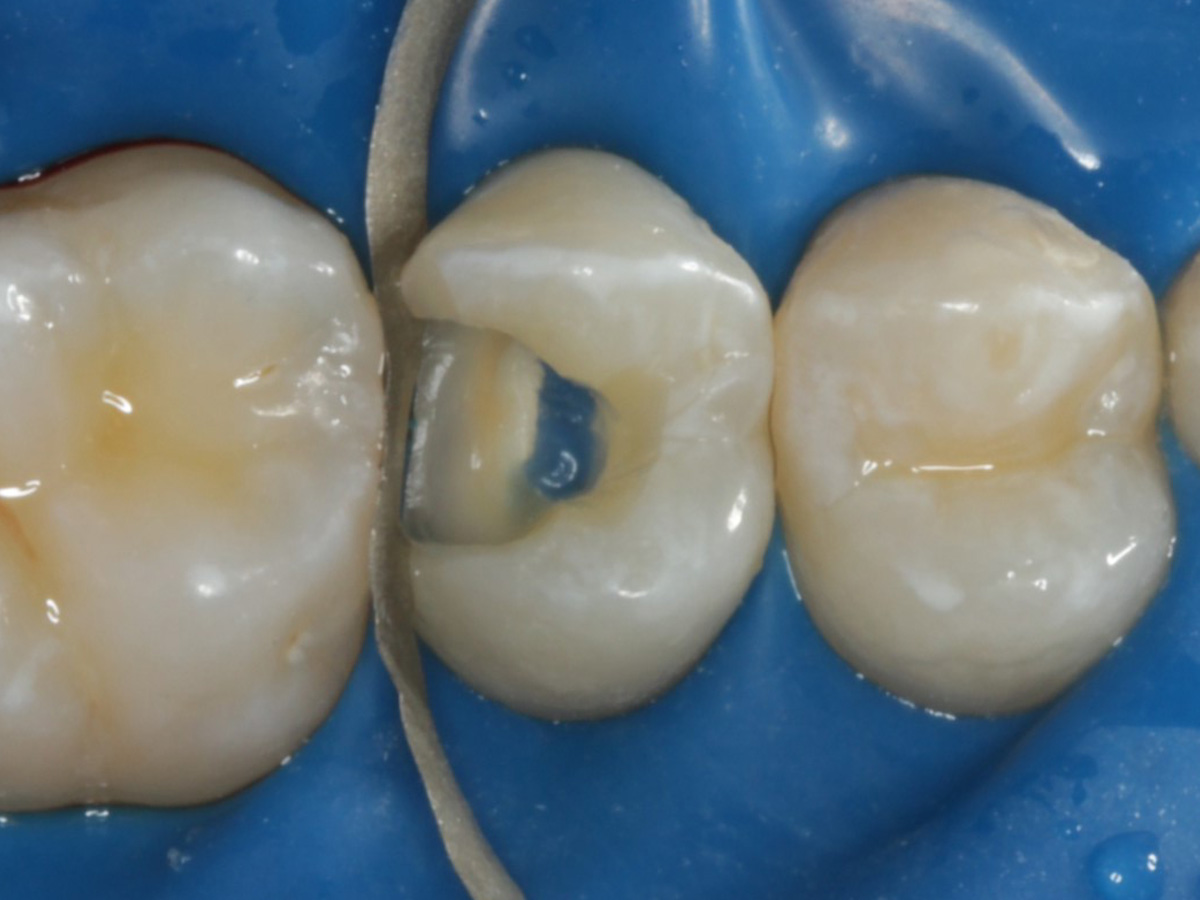

Abbildung 24

Folgesitzung: Trepanation Zahn 25